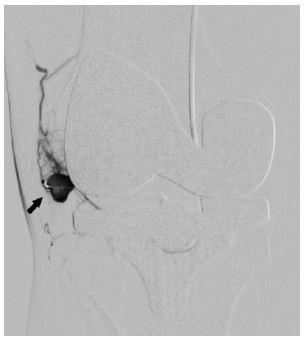

Figure 3: Angiography done through catheter in popliteal artery shows pseudoanuerysm (Solid arrow) arising from inferior medial geniculate artery (thin arrow).